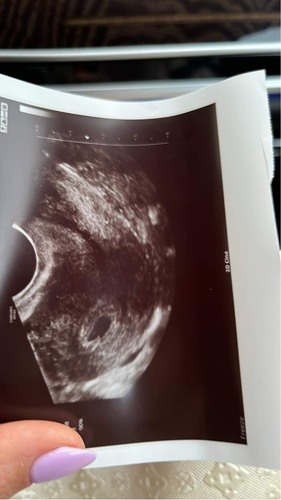

Mijn echo op 5 weken (wit stipje is het vruchtje) maar heb ook menstruatie krampen en wat verlies maar dit kan tot u 3 maanden duren